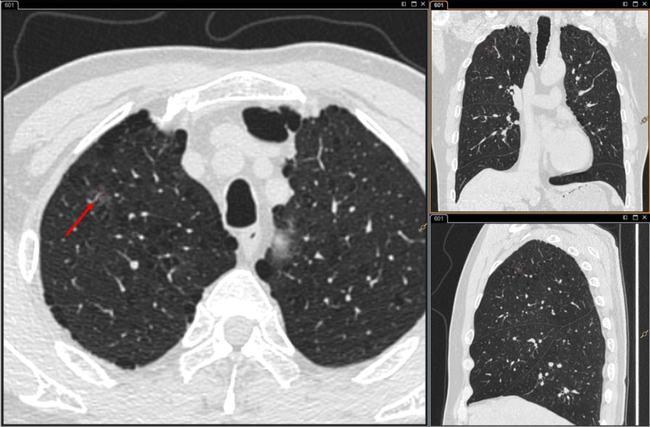

患者肺部ct影像显示结节